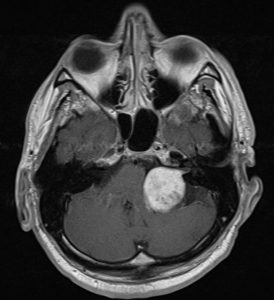

Ασθενής άνδρας, 52 ετών με κώφωση αριστερά και ιλιγγική συνδρομή.

Η μαγνητική τομογραφία εγκεφάλου ανέδειξε χωροκατακτητική εξεργασία στην αριστερή γεφυροπαρεγκεφαλιδική γωνία συμβατή με ακουστικό νευρίνωμα (αιθουσαίο σβάννωμα) και πίεση επί του στελέχους (Koos IV).